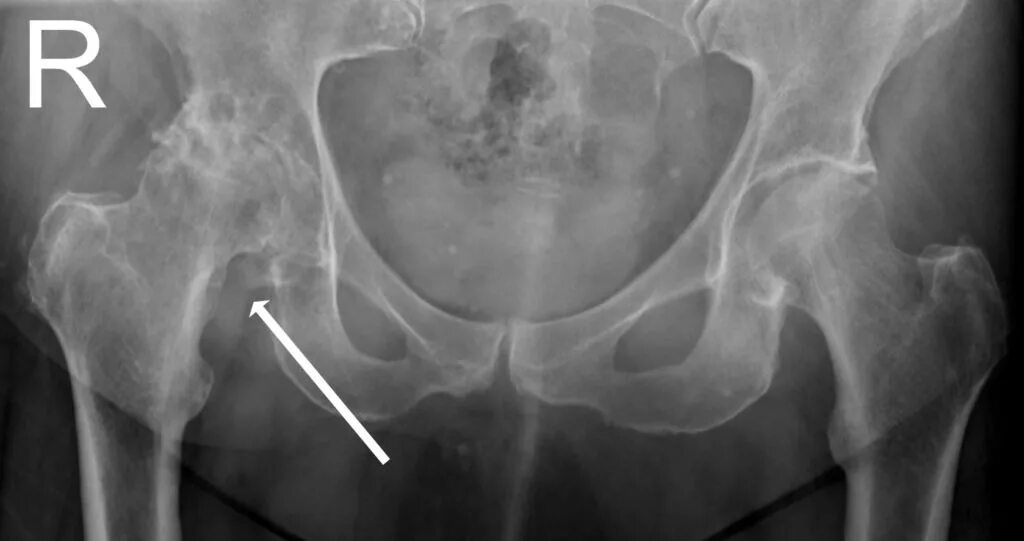

Артрит тазобедренного сустава симптомы